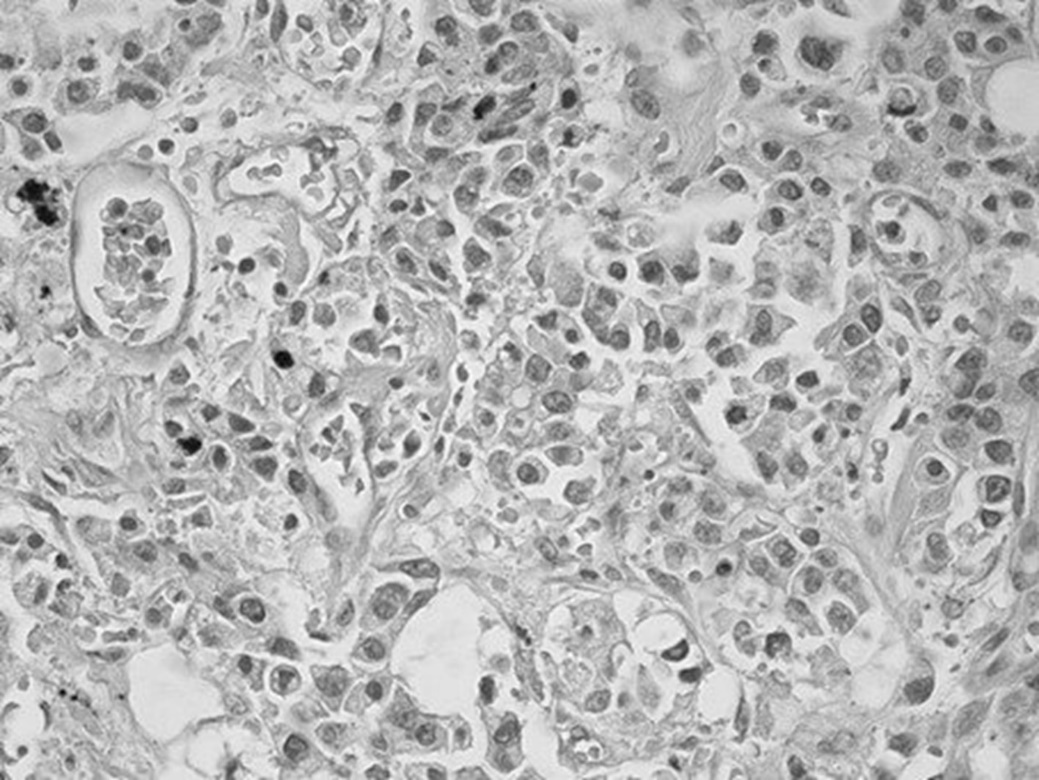

Ниже приводим результат посмертного гистологического исследования ткани печени: «Опухоль представлена полями крупных клеток, не формирующих упорядоченные трабекулярные структуры, с крупными ядрами. Во многих клетках – фигуры митоза, в том числе атипические. Ядра клеток характеризуются выраженным полиморфизмом, многие из них содержат крупные эозинофильные ядрышки. Наряду с атипией и высокой митотической активностью отмечается высокий ядерно-цитоплазматический коэффициент (соотношение площади ядра и цитоплазмы). Клетки располагаются как группами, так и изолированно, разделены узкими прослойками стромы (рис. 2). Опухолевая ткань с обильной васкуляризацией (рис. 3). Во многих сосудах встречаются опухолевые эмболы (рис. 4). Гистологическое заключение: низкодифференцированная гепатоцеллюлярная карцинома (G3), мультифокальный рост опухоли».

Рис. 2. Выраженный клеточный и ядерный полиморфизм, высокое ядерно-цитоплазматическое соотношение. Окраска гематоксилином и эозином, ув. 400